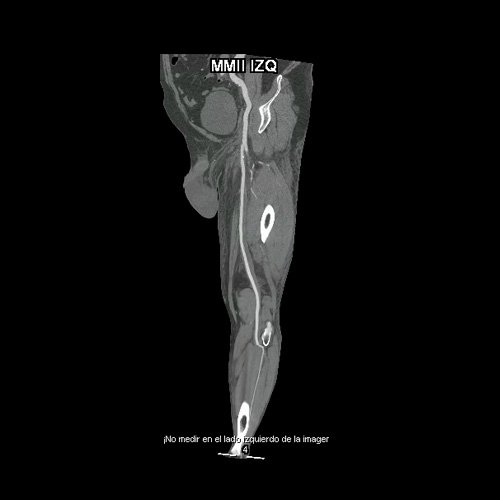

• AngioTAC de miembros inferiores (Día 0): Ateromatosis parietal calcificada parcheada en todo el territorio aorto-ilíaco-femoral bilateral. LADO DERECHO: Arteria ilíaca interna: de calibre y trayecto conservado, permeable. Arterias ilíaca externa y femoral común: de calibre y trayecto conservados, permeables. Arterias circunfleja ilíaca superficial y epigástrica superficial: de calibre y trayecto conservados, permeables. Arteria femoral superficial: de calibre y trayecto conservado, permeable. Arteria femoral profunda: de calibre y trayecto conservado, permeable. Arterias circunflejas femoral medial y lateral: de calibre y trayecto conservados, permeables. Arteria poplítea: de calibre y trayecto conservado, permeable. Arteria tibial anterior: de calibre y trayecto conservado, permeable. Arteria tibial posterior: de calibre y trayecto conservado, permeable. Cambios artrodegenerativos coxo-femorales y tricompartimentales en la rodilla. Signos de entesopatía cuadricipital distal. No se observan alteraciones a nivel de los grupos musculares visualizados. La disposición del tejido graso es normal. LADO IZQUIERDO: En fase angiográfica se observa menor calibre y opacificación de las arterias femoral superficial y profunda, poplítea y de sus ramas musculares en muslo y pierna en comparación con el miembro contralateral, con opacificación arterial preservada. En fase venosa se evidencia mayor la densidad endovascular de las mismas hasta el tercio distal de la pierna, donde se logran identificar a las arterias peronea, tibial anterior y tibial posterior. Se evidencia un defecto de relleno de la vena ilíaca común izquierda, en su nacimiento, en relación a trombosis venosa profunda. No se identifica compromiso de la porción visualizada de la vena cava inferior ni del sistema venoso ilíaco contralateral. Se visualiza aumento del tamaño de todos los grupos musculares del muslo izquierdo con respecto al contralateral y retardo de la concentración de contraste, asociado a edema de los tejidos blandos superficiales. Reticulación de la grasa de la región inguinal. Cambios artrodegenerativos coxo-femorales y tricompartimentales en la rodilla. Signos de entesopatía cuadricipital distal. No se observan alteraciones a nivel del fémur ni de las porciones visualizadas de la tibia y el peroné.

• AngioTAC de miembros inferiores (Día 2): Ateromatosis parietal calcificada parcheada en todo el territorio aorto-ilíaco-femoral bilateral. LADO DERECHO: Arteria ilíaca interna: de calibre y trayecto conservado, permeable. Arterias ilíaca externa y femoral común: de calibre y trayecto conservados, permeables. Arterias circunfleja ilíaca superficial y epigástrica superficial: de calibre y trayecto conservados, permeables. Arteria femoral superficial: de calibre y trayecto conservado, permeable. Arteria femoral profunda: de calibre y trayecto conservado, permeable. Arterias circunflejas femoral medial y lateral: de calibre y trayecto conservados, permeables. Arteria poplítea: de calibre y trayecto conservado, permeable. Arteria tibial anterior: de calibre y trayecto conservado, permeable. Arteria tibial posterior: de calibre y trayecto conservado, permeable. Vena ilíaca primitiva: 13 mm, vena ilíaca externa 11 mm, vena ilíaca interna 7 mm. LADO IZQUIERDO: En esta ocasión, en fase angiográfica se observa de calibre y opacificación conservada de las arterias femoral superficial y profunda, poplítea y de sus ramas musculares en muslo y pierna. En fase venosa se evidencia un defecto de relleno endoluminal de la vena primitiva izquierda que impresiona extenderse actualmente a la vena iliaca externa, a la vena femoral superficial y poplítea, hasta nivel del hueco homonimo, las cuales se visualizan aumentadas de calibre con respecto a sus contralaterales, en relación a trombosis venosa profunda. Se sugiere cotejar con ecodoppler de miembros inferiores. No se identifica compromiso de la porción visualizada de la vena cava inferior ni del sistema venoso ilíaco contralateral. Se visualiza dispositivo vascular en VCI (filtro VCI), infrayacente a las venas renales. Presenta aumento del diámetro del muslo izquierdo con respecto a su contralateral, asociado a edema de los tejidos blandos superficiales. Reticulación de la grasa de la región inguinal a predominio izquierdo con algunas burbujas aéreas. Se observa inmediatamente infrayacente a los antes mencionado, un área hiperdensa que realza en fase venosa, con centro hipodenso, que mide 2.2 cm x 1.4 cm, ya visualizado en tomografía previa. Cambios artrodegenerativos coxo-femorales y tricompartimentales en la rodilla. Signos de entesopatía cuadricipital distal. No se observan alteraciones a nivel del fémur ni de las porciones visualizadas de la tibia y el peroné. Arteria ilíaca interna: de calibre y trayecto conservado, permeable. Arterias ilíaca externa y femoral común: de calibre y trayecto conservados, permeables. Arterias circunfleja ilíaca superficial y epigástrica superficial: de calibre y trayecto conservados, permeables. Arteria femoral superficial: de calibre y trayecto conservado, permeable. Arteria femoral profunda: de calibre y trayecto conservado, permeable. Arterias circunflejas femoral medial y lateral: de calibre y trayecto conservados, permeables. Arteria poplítea, tibial anterior y tibial posterior: de calibre disminuido con respecto a su contralateral, permeables. Vena ilíaca primitiva: 14 mm, vena ilíaca externa 17 mm, vena ilíaca interna 9 mm. Calcificaciones en conducto inguinal bilateral. Hidrocele bilateral.

Angio TAC de miembros inferiores (Día 0)

Angio TAC de miembros inferiores (Día 2)